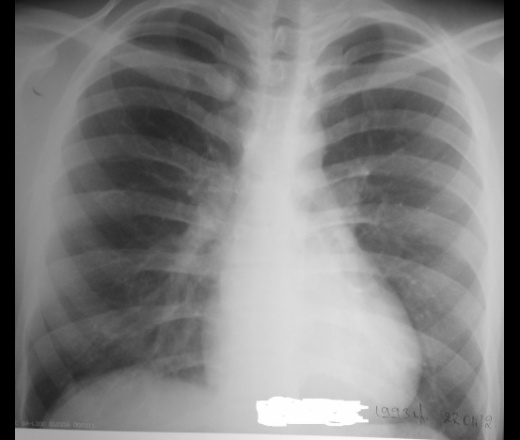

Молодой мужчина две недели тому назад пришёл на снимок для исключения пневмонии. Снимок сделали, он же прилагается. Инфильтрации не нашли. Через две недели снова приходит для исключения пневмонии справа. СОЭ 60, сильные боли в правом боку. Сделали две проекции, диафрагма стоит высоко справа. Рекомендовал провести УЗИ для исключения поддиафрагмального абсцесса. Что можете сказать по снимку уважаемые коллеги и по ситуации в целом?

Гидроторакс справа (наддиафрагмальный). Пунктируйте....

А, на мой взгляд, так тут правосторонний базальный выпот.

Наддиафрагмальный с большай вероятностью. А междолевой мы выставляем только после боковой томографии, ибо, всевозможные наложения могут подвести. Но "затек" в междолевку, конечно, не исключается.

Вид синусов справа с их пологостью и плавностью свидетельствуют о наличии выпота. А, в положении лежа, надо думать, что мал-мал растечется выпот, ну, и изменит форму.

Да, Валентин Львович, Вы совершенно правы. УЗИ-ст посмотрел плевральную полость, определил наличие экссудата. Был поставлен диагноз эмпиема плевры.